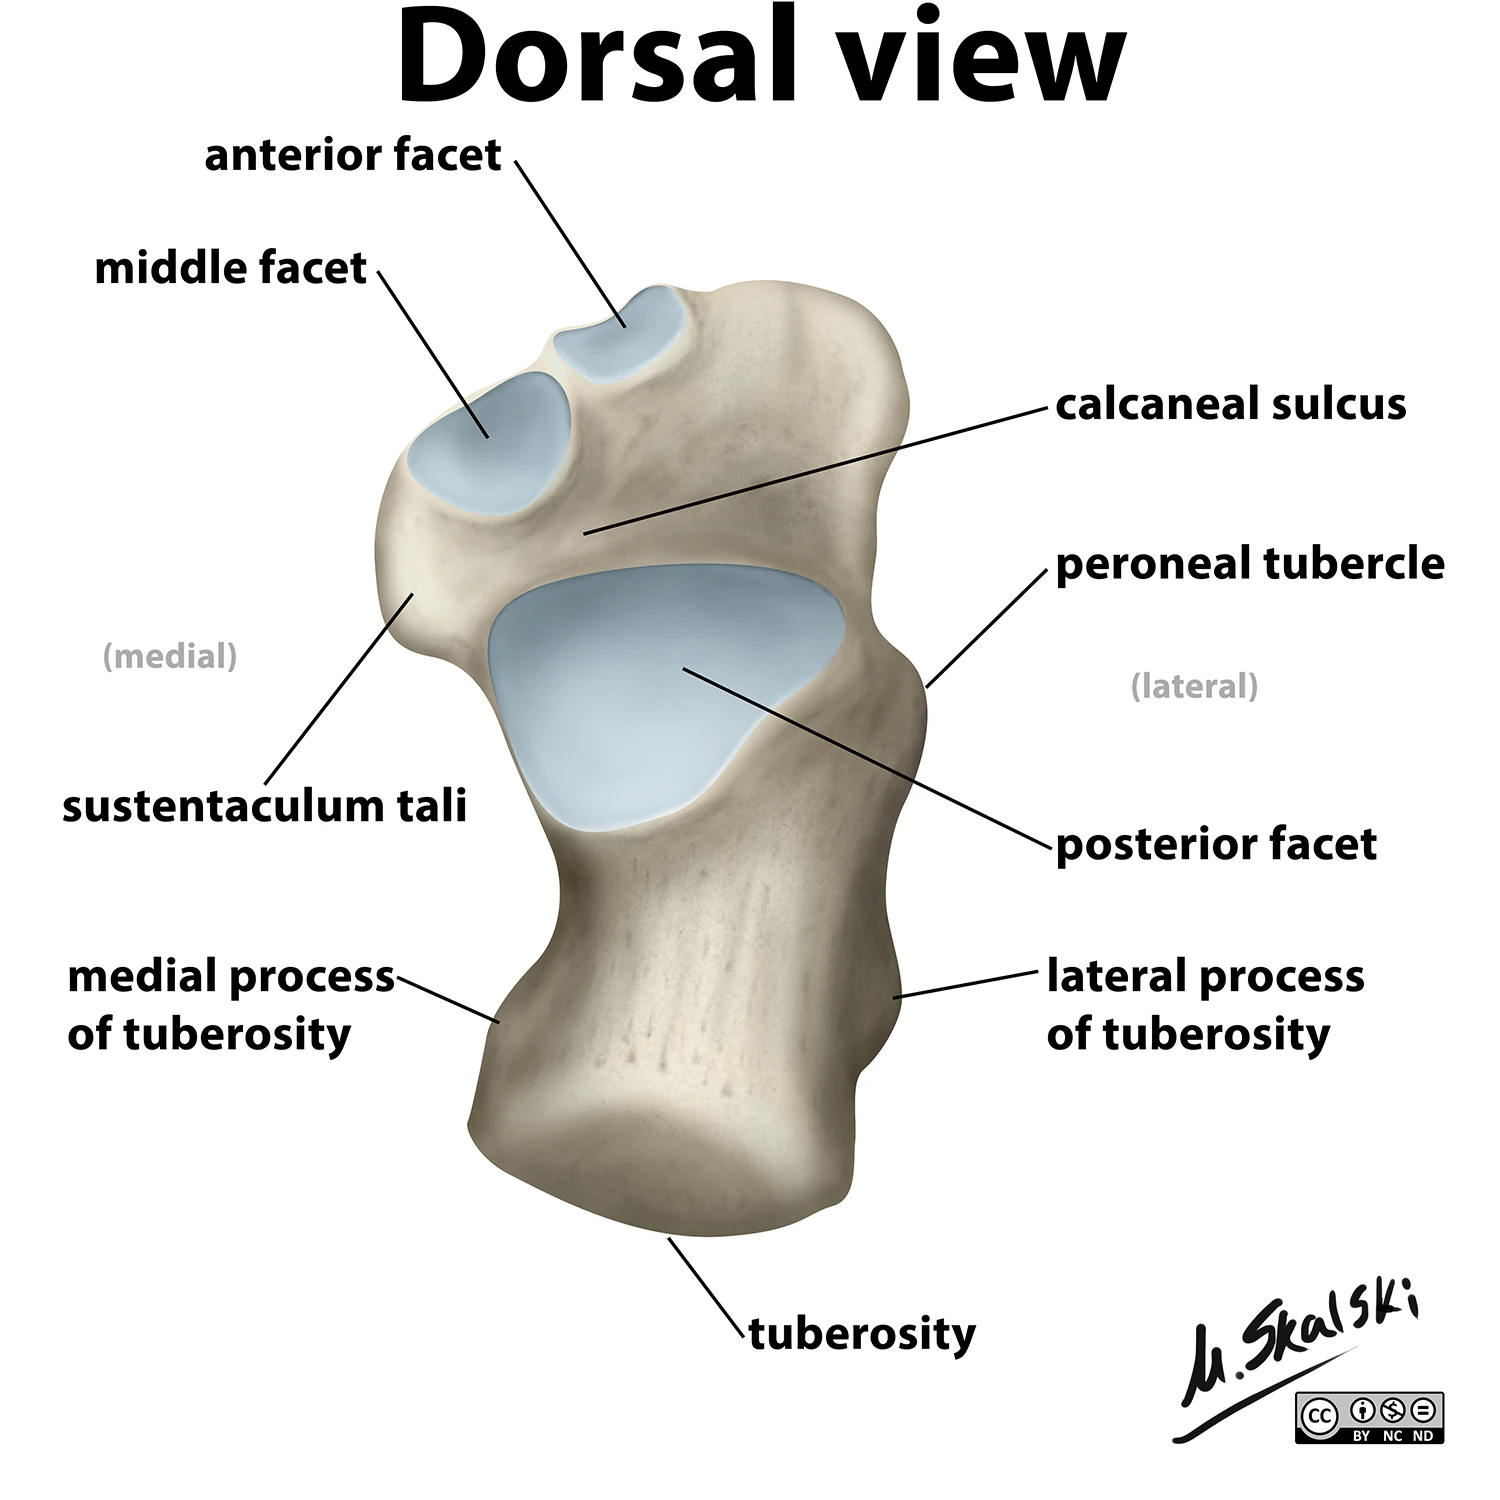

Label the 3 surfaces of the talus that articulate with the calcaneus